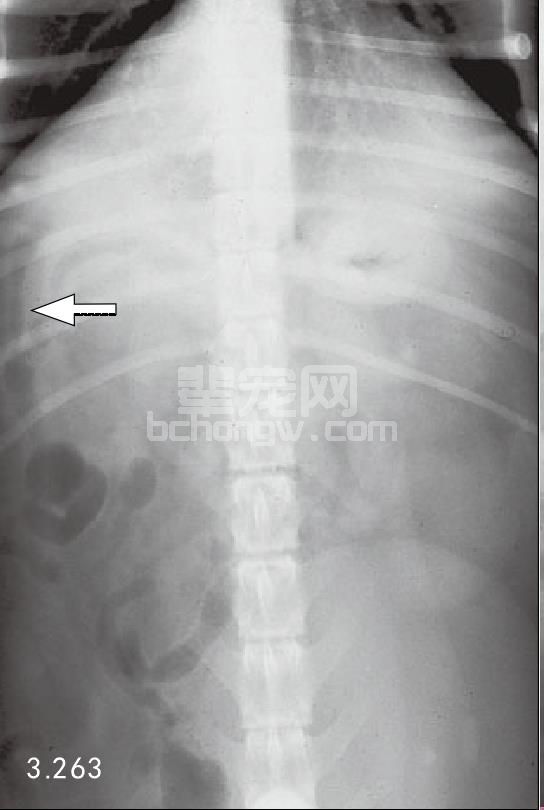

两种最常用方法是X线和超声波。犬和猫急性胰腺炎的腹部X线能显示几处异常。在轻度水肿时,可见包括胃和十二指肠从正常到轻度肠梗阻范围。更严重时,由于腹膜炎会导致以下变化:在腹腔前部由于液体密度增加,使内脏详细影像消失,右侧十二指肠移位和胃扩张。除这些典型症状外,急性胰腺炎X线显示胸腔渗漏液和肺部积液(图3.262和图3.263)。

图3.262和图3.263 犬患有急性胰腺炎的几种异常的侧面和腹背面的X线片,侧面投影(图3.262)显示腹中前部不清楚,腹前部液体密度增加,从末端到肝脏(箭头所指)。腹背面X片(图3.263)可见与十二指肠梗阻一起,单侧右上腹部液体密度增加。